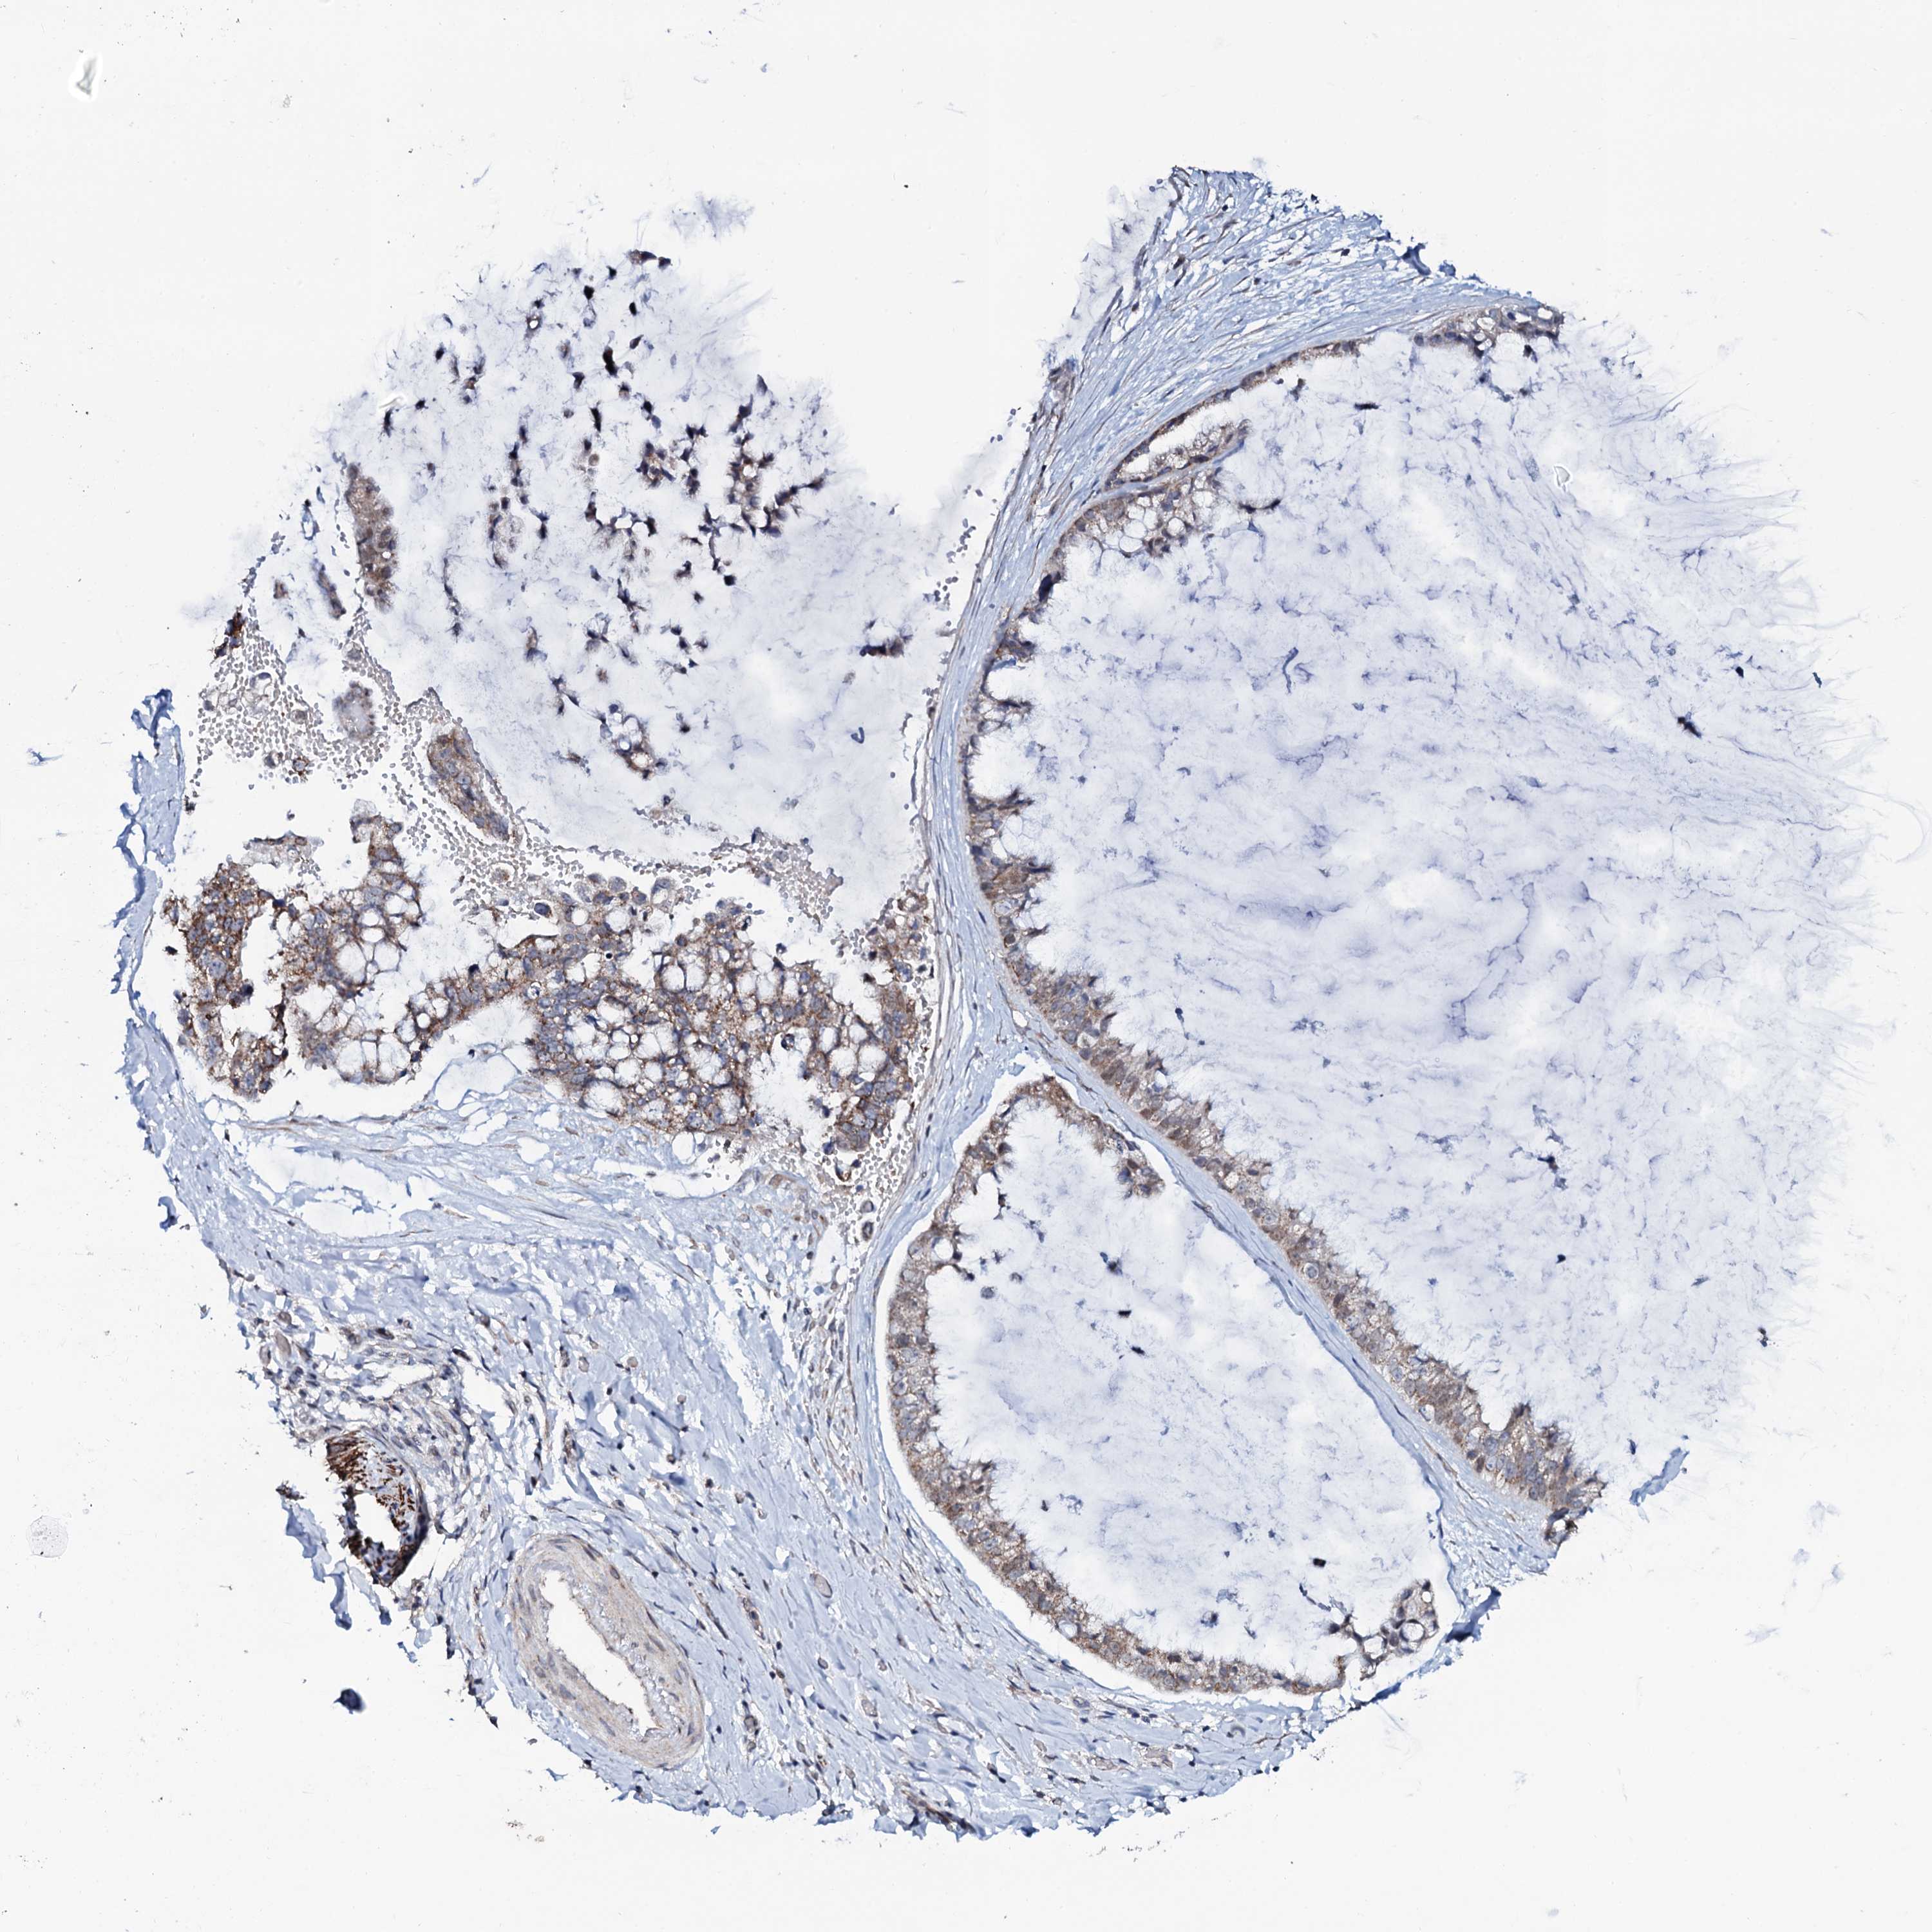

OVARIAN CANCER - Protein expressioni

A mouse-over function shows sample information and annotation data. Click on an image to view it in a full screen mode. Samples can be filtered based on level of antibody staining by selecting one or several of the following categories: high, medium, low and not detected. The assay and annotation is described here.

Note that samples used for immunohistochemistry by the Human Protein Atlas do not correspond to samples in the TCGA dataset.

Antibody stainingi

Antibody staining in the annotated cell types in the current human tissue is reported as not detected, low, medium, or high, based on conventional immunohistochemistry profiling in selected tissues. This score is based on the combination of the staining intensity and fraction of stained cells.

Each image is clickable and will lead to virtual microscopy that enables deeper exploration of all samples and also displays staining intensity scores, fraction scores and subcellular localization as well as patient and tissue information for each sample.

Antibody HPA041146

Staining

High

Medium

Low

Not detected

Intensity

Strong

Moderate

Weak

Negative

Quantity

>75%

75%-25%

<25%

None

Location

Nuclear

Cytoplasmic/membranous

Cytoplasmic/membranous,nuclear

Cystadenocarcinoma, serous, NOS

Carcinoma, endometroid

Cystadenocarcinoma, mucinous, NOS

Carcinoma, NOS